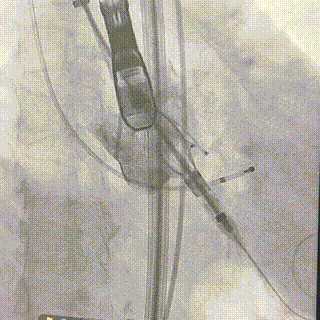

2026年伊始,TaurusTrio经导管主动脉瓣系统在武汉大学人民医院,中国科学技术大学附属第一医院,安徽医科大学第一附属医院,安徽医科大学第一附属医院北区,首都医科大学附属北京安贞医院南充医院,海南省人民医院等多家临床中心成功开展上市后全国首批植入。这不仅是TaurusTrio正式走向广泛临床应用的重要里程碑,更标志着中国单纯主动脉瓣反流介入治疗正式迈入了“心键合璧”的全新纪元。